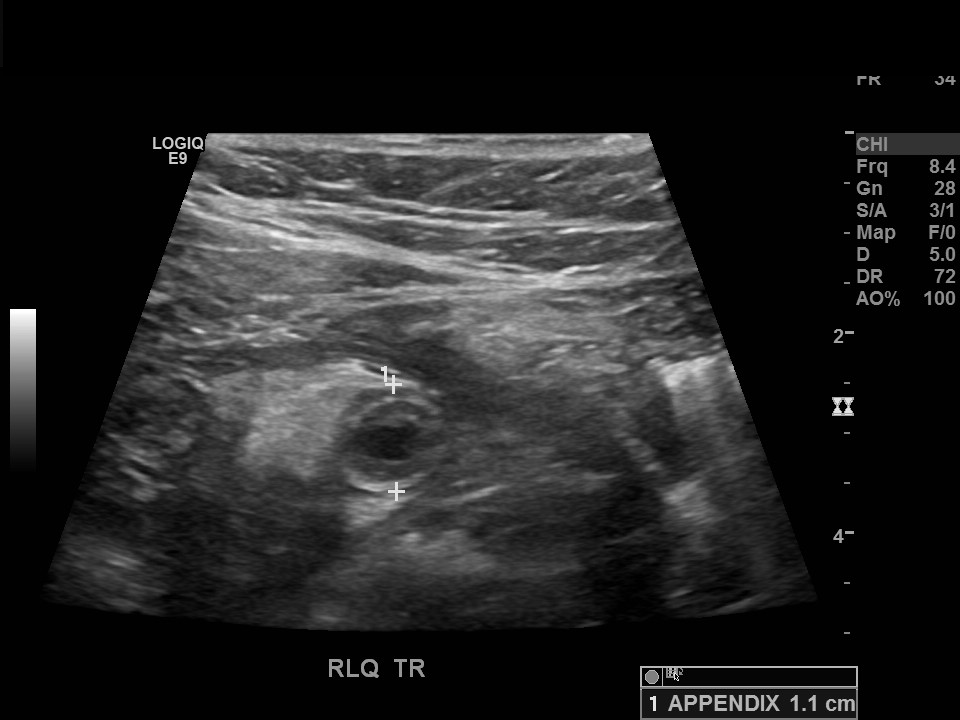

Appendicitis 5

1.5 cm appendicitis with hyperemia.